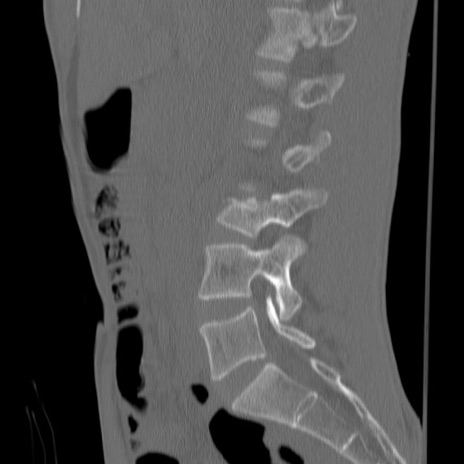

症例3 腰椎CT(矢状断像)

【症例】30歳代男性

【主訴】腰痛

【現病歴】本日旅行先で観光中に、友人と衝突し転倒し受傷。

【身体所見】麻痺なし、右下腿内側前面外側、左下腿内側に知覚鈍麻・しびれ

異常所見と診断は?

腰椎CT